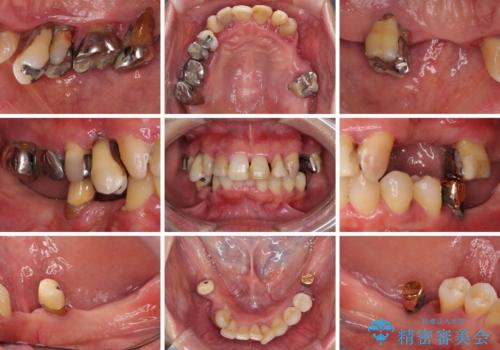

- 歯周病を放置したことで奥歯が抜け、前歯も痛くなってきたとのことで来院された患者様です。

奥歯はほとんどを抜歯しなければならない状態であり、抜歯をせずに済む歯も歯周外科処置や矯正治療を行う必要がある状態でした。

歯を抜かないといけない部分はインプラントとオールセラミッククラウンにより咬合を回復させ、歯周外科処置を行う歯については、同じくオールセラミッククラウンにて補綴治療を行うこととしました。

外科処置を多く行ったため、その待ち時間が長くかかり、さらには途中矯正治療も行なったので、治療期間は長期間となりました。